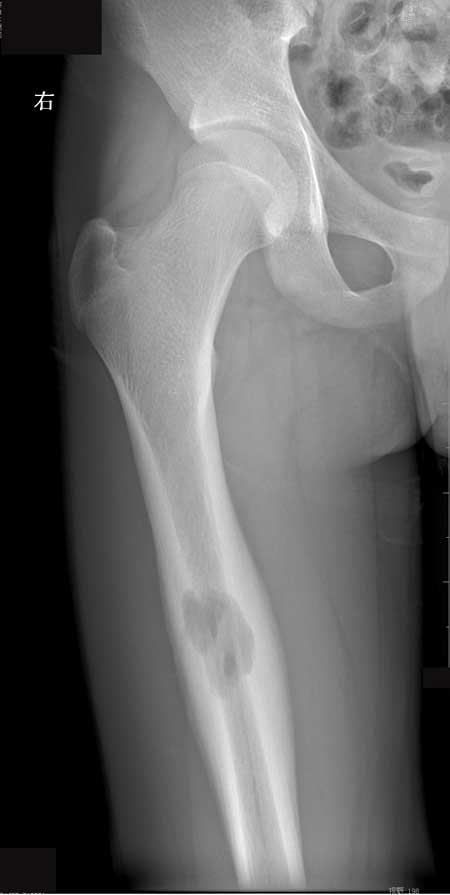

右股骨干嗜酸性肉芽肿

M23岁,右侧大腿疼痛两月余,无其他~~~

【zxl51642】良性肿瘤样病变,考虑Langerhands组织细胞增生症(嗜酸性肉芽肿)。

【ZHANGZHONGSHOU】嗜酸性肉芽肿可能性大,囊状骨质破坏,累及骨皮质,骨膜增生、骨皮质增厚,连续、无破坏,范围常于骨破坏范围,患者青年均支持嗜酸性肉芽肿可能性大。

【黑白光影】好发的年龄,孤立而界限分明的溶骨性缺损,偏于一侧的骨膜反应,考虑嗜酸性肉芽肿可能性大。

【wudaodong2008 】骨髓腔反应范围较大界限模糊、皮质增厚广泛 骨膜反应明显但层次不清-----符合炎性改变;瘤子不考虑。

病理报告:(右股骨中上段肿物)符合嗜酸性肉芽肿